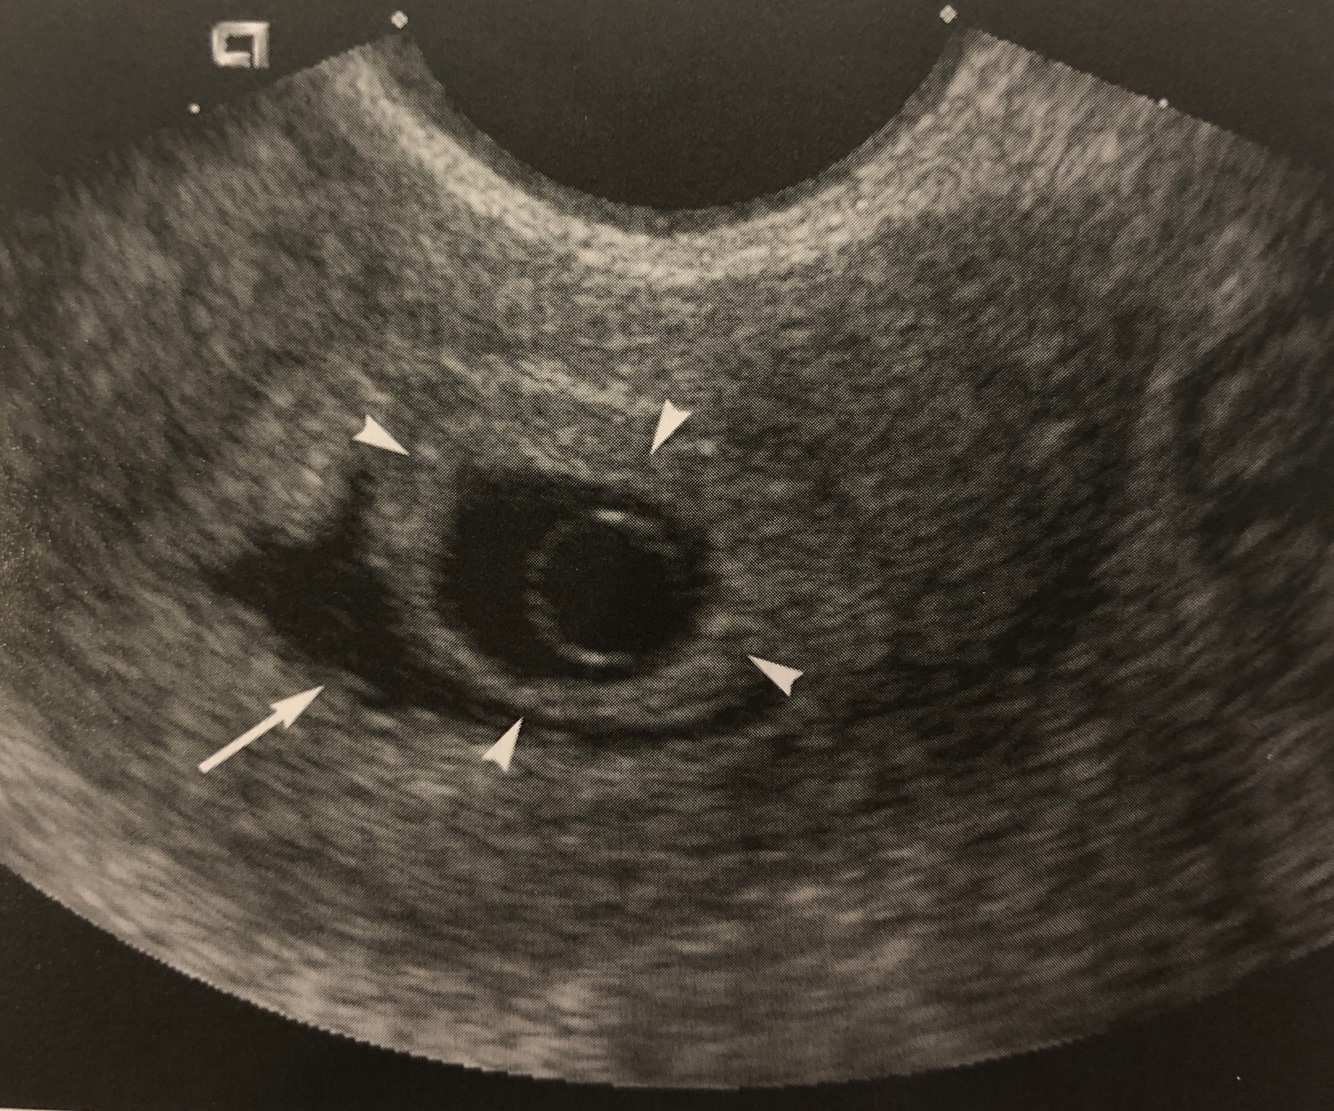

A bleed between the endometrium and gestational sac

A

Subchorionic hemorrhage

20

Q

Anechoic, crescent shaped area adjacent to gestational sac

21

The long arrow is pointing to